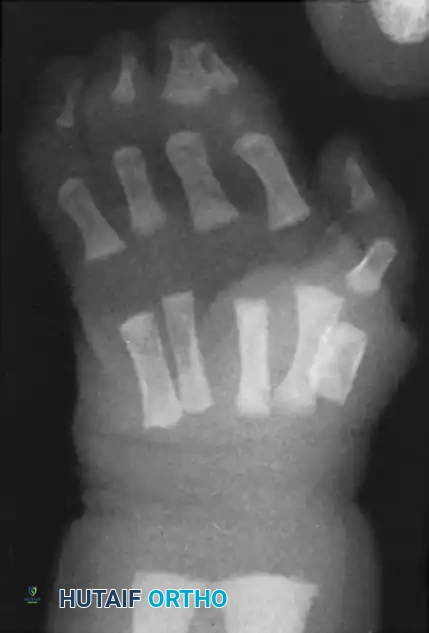

Image

Figure: Simple syndactyly, palmar view. Fingers are bridged only by skin and soft tissues.

Figure: Simple syndactyly, dorsal view.

Figure: Radiograph of simple syndactyly. Note the angular deformity beginning to develop in the ring finger.